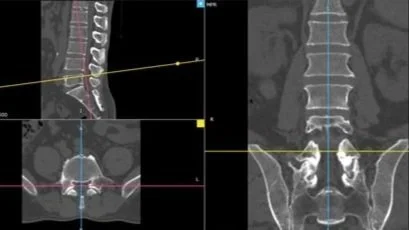

Orient the CT slide as seen in the example below: